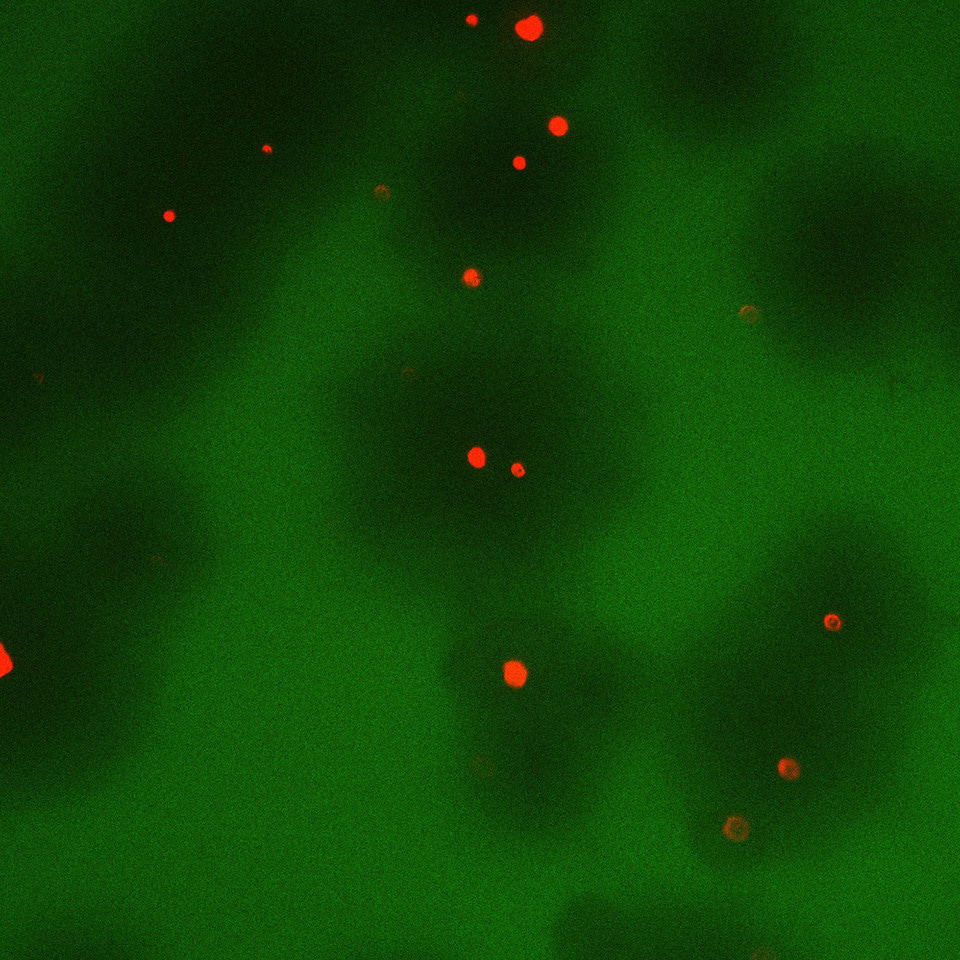

Figure 1: Overall concept of phage therapy for bacterial lung infection. Reproduced from our paper2. SpringerNature.